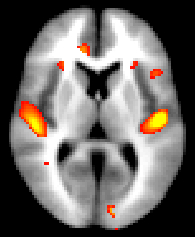

You can then view the (1-p) corrected p-value images in FSLView:

Then you can threshold your _clustere_corrp_ images (corrected p-values maps) at 0.95 to keep only the significant clusters and use it to mask the corresponding tstats map:

fslmaths fslvbm_clustere_corrp_tstat1 -thr 0.95 -bin mask_pcorrected

fslmaths fslvbm_tstat1 -mas mask_pcorrected fslvbm_tstat1_corrected

before displaying it with fsleyes overlaid on the template_GM or the MNI152 template for example: